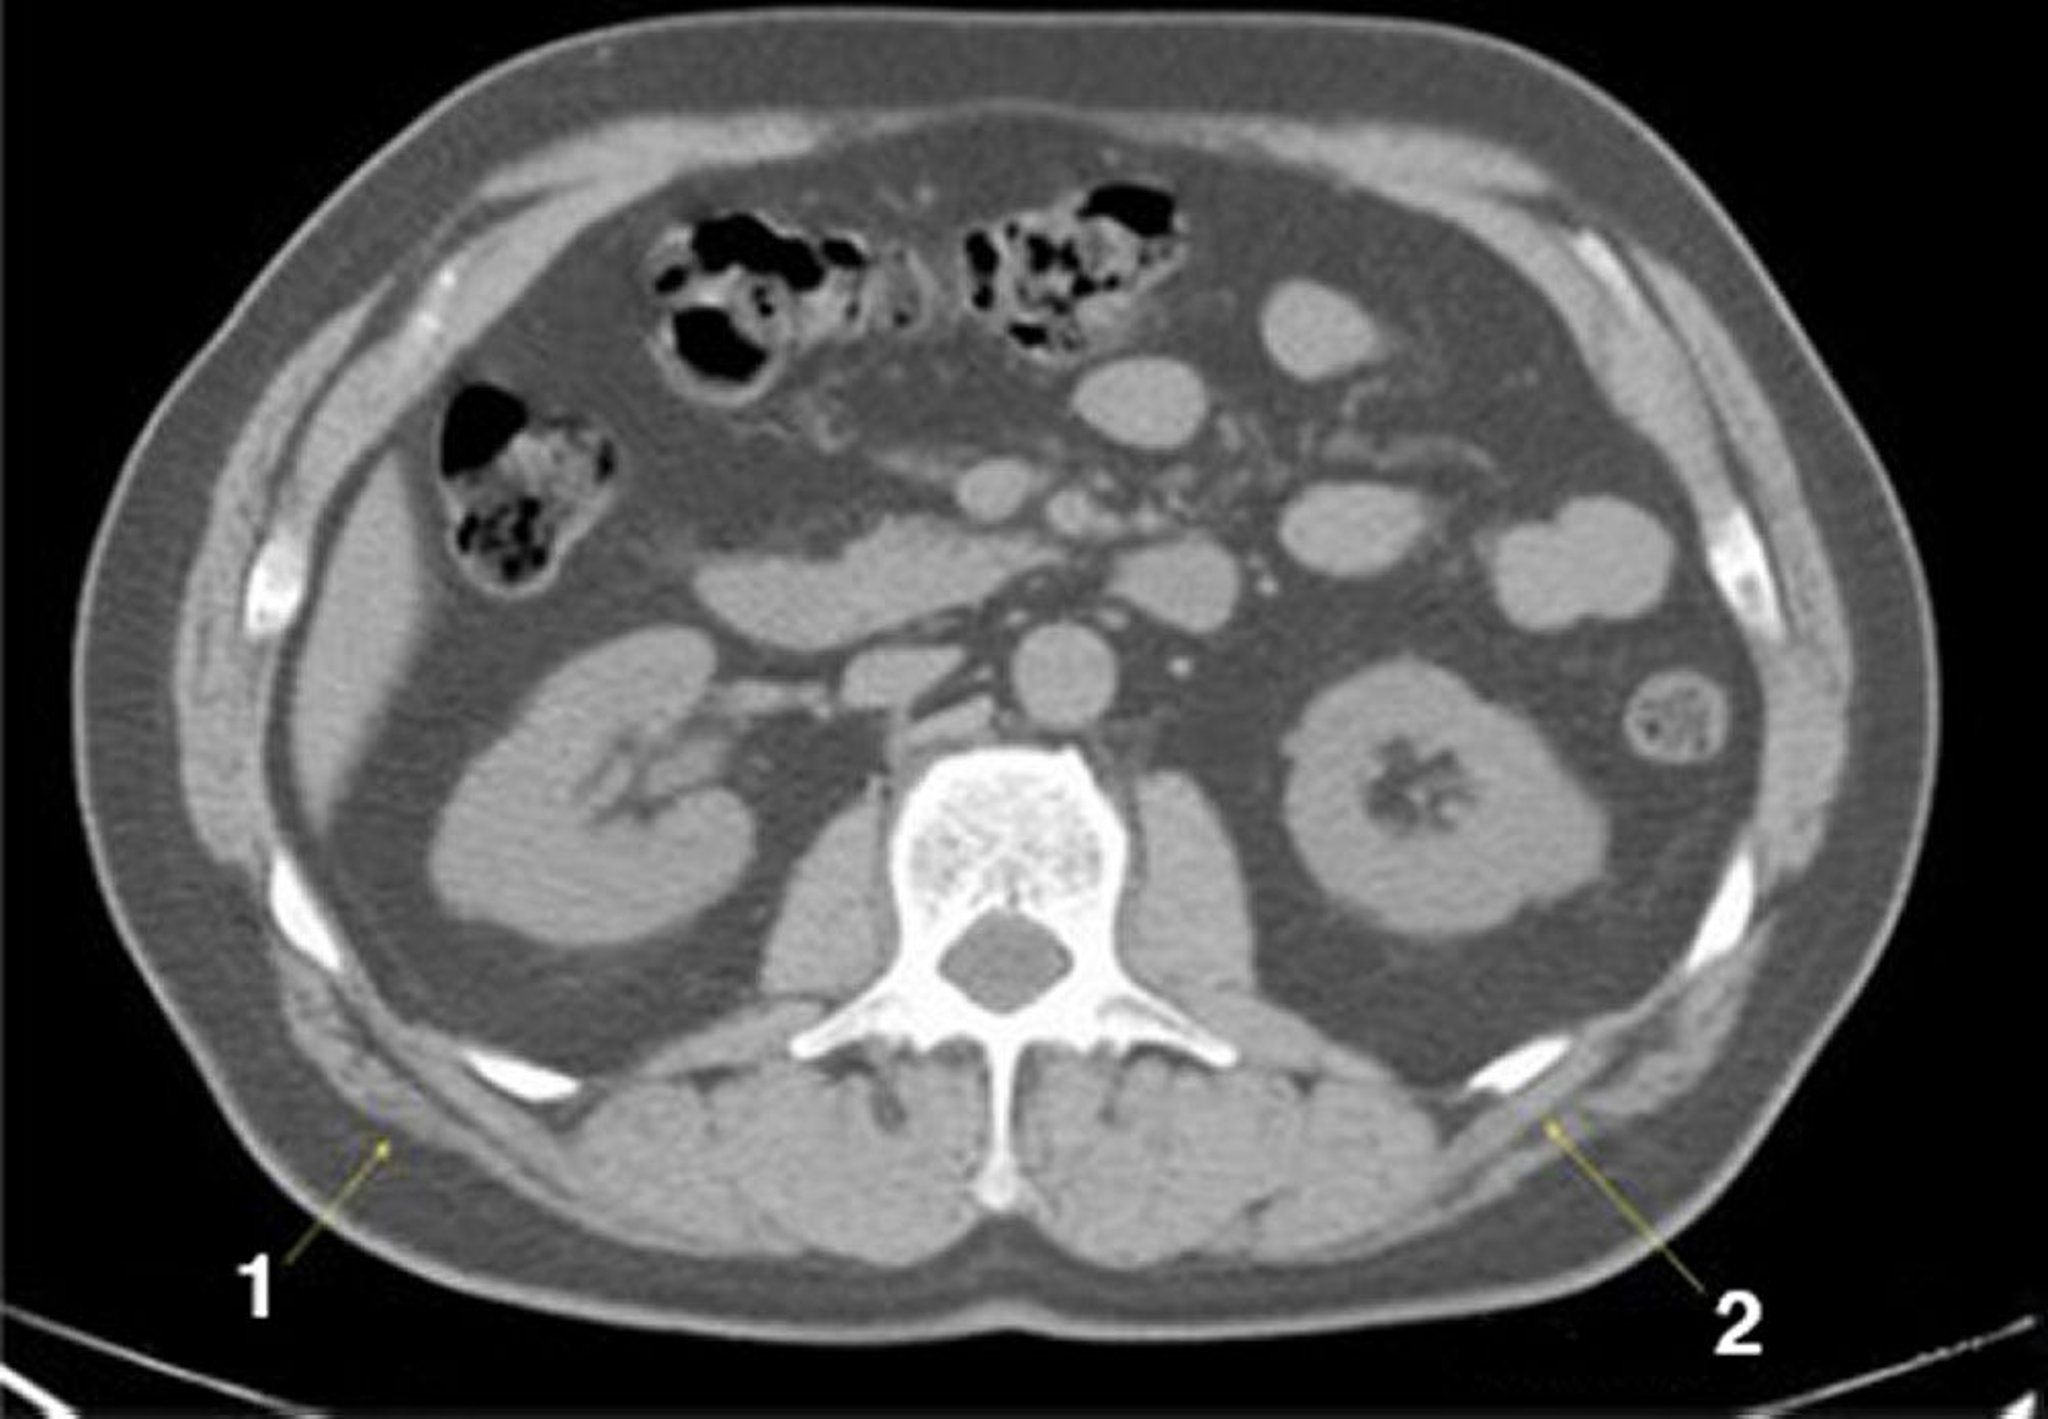

TC sem contraste do abdome e da pelve mostrando anatomia normal (lâmina 15)

1 = latíssimo do dorso; 2 = serrátil posterior.